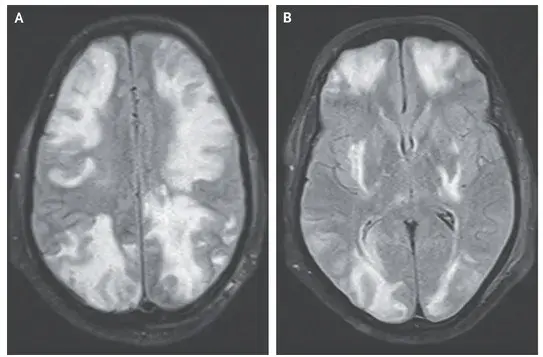

Cefalea, alteración visual y convulsión en un paciente con nefropatía por IgA

Caso clínico publicado en el NEJM: Un hombre de 35 años con nefropatía por IgA acudió a urgencias con síntomas de confusión mental, visión borrosa y convulsiones durante 1 día. Dos semanas antes de la presentación, comenzó a tomar ciclosporina para el tratamiento de la nefropatía por IgA. Su presión arterial era de 160/80 mm Hg. En el examen físico, el paciente estaba somnoliento y presentaba disminución de la agudeza visual. El examen de fondo de ojo fue normal.